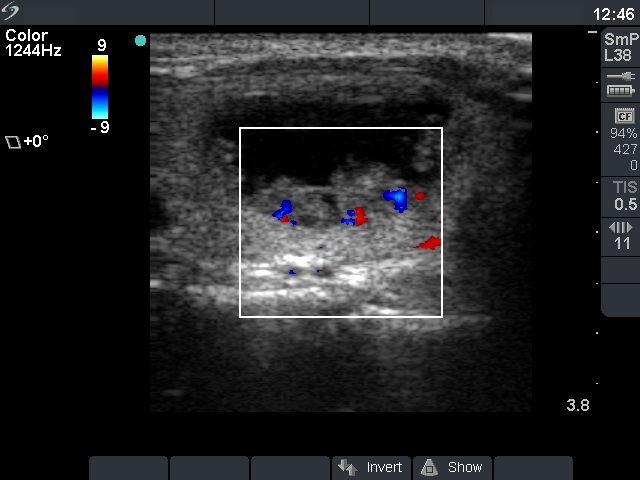

| The presence of microcalcifications and

the type 3 vascular pattern increased the possibility of being this

nodule malignant. |

The lack of vascularization on Doppler

mode has no relevance in the differential diagnostic of nodular

goiters. |